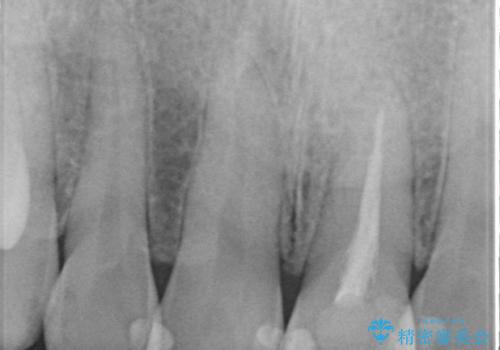

- 前歯の長さが気になるのでセラミックで治療したいといらっしゃった方の症例です。

御希望された再根管治療終了後、オールセラミッククラウンによる補綴を行いました。

今回用いたオールセラミッククラウンはジルコニアフレームという白い素材の上にセラミックを盛っているため、審美性が非常に高いのが特徴です。